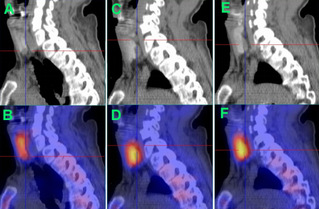

首先需要进一步明确定位功能亢进的甲状旁腺,该患者在苏州九院核医学科行99mTc-MIBI甲状旁腺显像。显像后诊断意见:甲状腺右叶下极下方、左叶上极背侧、左叶下极背侧结节显像剂异常浓聚,结合超声及实验室检查结果,均考虑为功能亢进甲状旁腺组织,余部位未见异常功能亢进甲状旁腺组织。

△99mTc-MIBI甲状旁腺显像图:A+B、C+D、E+F(矢状位CT+SPECT/CT融合显像)分别提示甲状腺右叶下极下方、甲状腺左叶上极背侧、甲状腺左叶下极背侧功能亢进甲状旁腺组织(十字线交叉处)